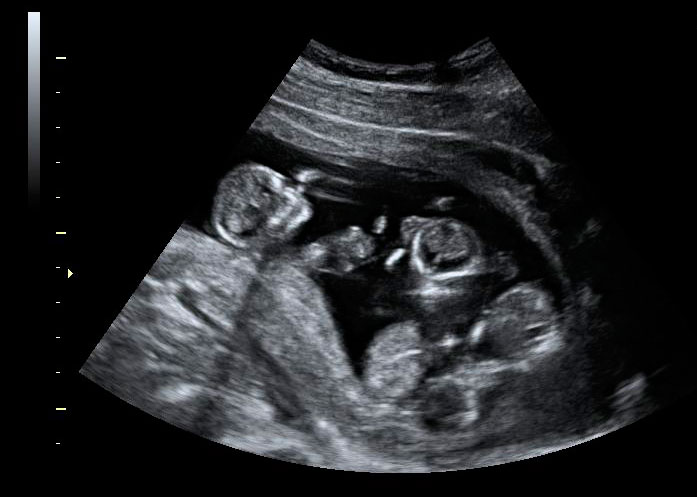

Embarazo triple en ecografía 2D

Esta ecografía en dos dimensiones (2D) muestra la imagen de tres fetos, uno en la parte superior de útero y dos gemelos en la parte baja del mismo. La edad gestacional de los bebés es de 10 semanas y cinco días. Se percibe con claridad la separación de bolsa y placentas entre el feto único (arriba a la izquierda) y sus hermanos gemelos, localizados en la esquina inferior derecha de la imagen.